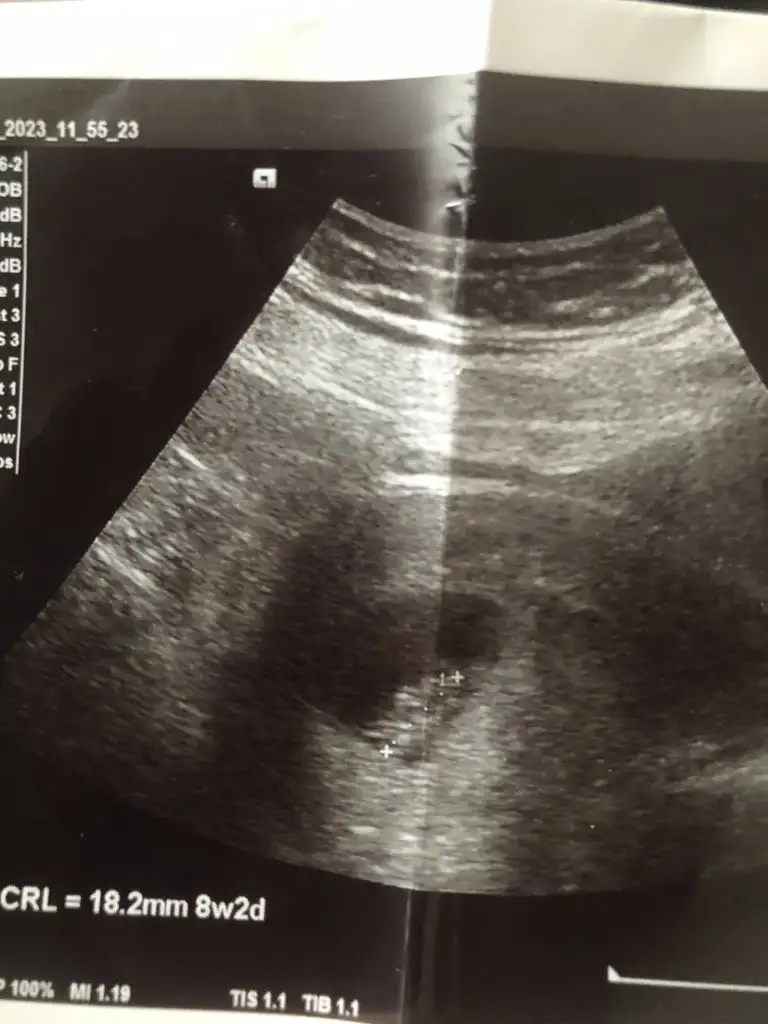

Merhaba benşm içinde tahminde bulunurmusunuz 🫶 8 haftalık karından usg

• IMG_7704.webp

IMG_7704.webp

28,5 KB · Görüntüleme: 111